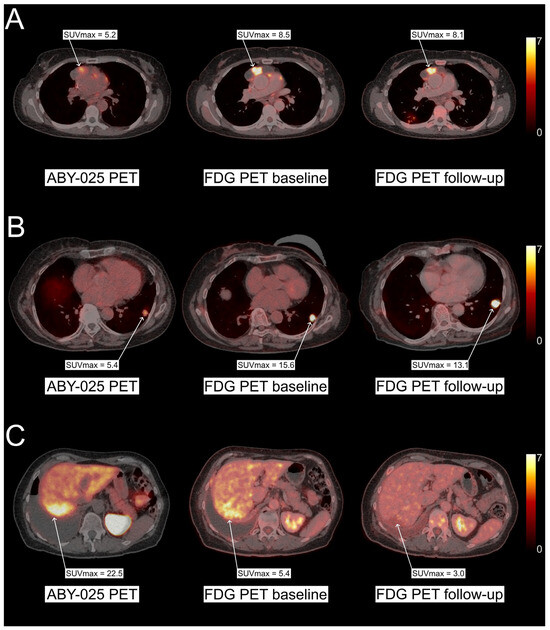

- Alhuseinalkhudhur, A.; Lindman, H.; Liss, P.; Sundin, T.; Frejd, F.Y.; Hartman, J.; Iyer, V.; Feldwisch, J.; Lubberink, M.; Ronnlund, C.; et al. Human Epidermal Growth Factor Receptor 2-Targeting [(68)Ga]Ga-ABY-025 PET/CT Predicts Early Metabolic Response in Metastatic Breast Cancer. J. Nucl. Med. 2023, 64, 1364–1370. [Google Scholar] [CrossRef]

- Sandberg, D.; Tolmachev, V.; Velikyan, I.; Olofsson, H.; Wennborg, A.; Feldwisch, J.; Carlsson, J.; Lindman, H.; Sorensen, J. Intra-image referencing for simplified assessment of HER2-expression in breast cancer metastases using the Affibody molecule ABY-025 with PET and SPECT. Eur. J. Nucl. Med. Mol. Imaging 2017, 44, 1337–1346. [Google Scholar] [CrossRef]